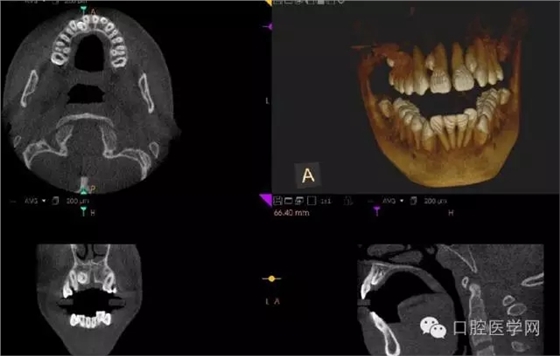

額外牙

X線表現(xiàn):最多見(jiàn)于上頜兩中切牙之間;圓錐形,根短小;拍攝X線片可確定額外牙的數(shù)目、位置、形態(tài)與鄰牙的關(guān)系。